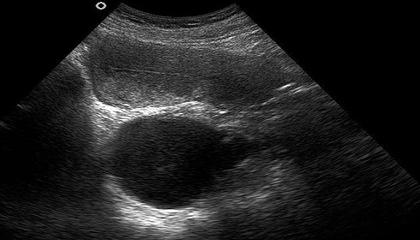

4、20至22周:超声波检查以鉴定胎儿是否正常。